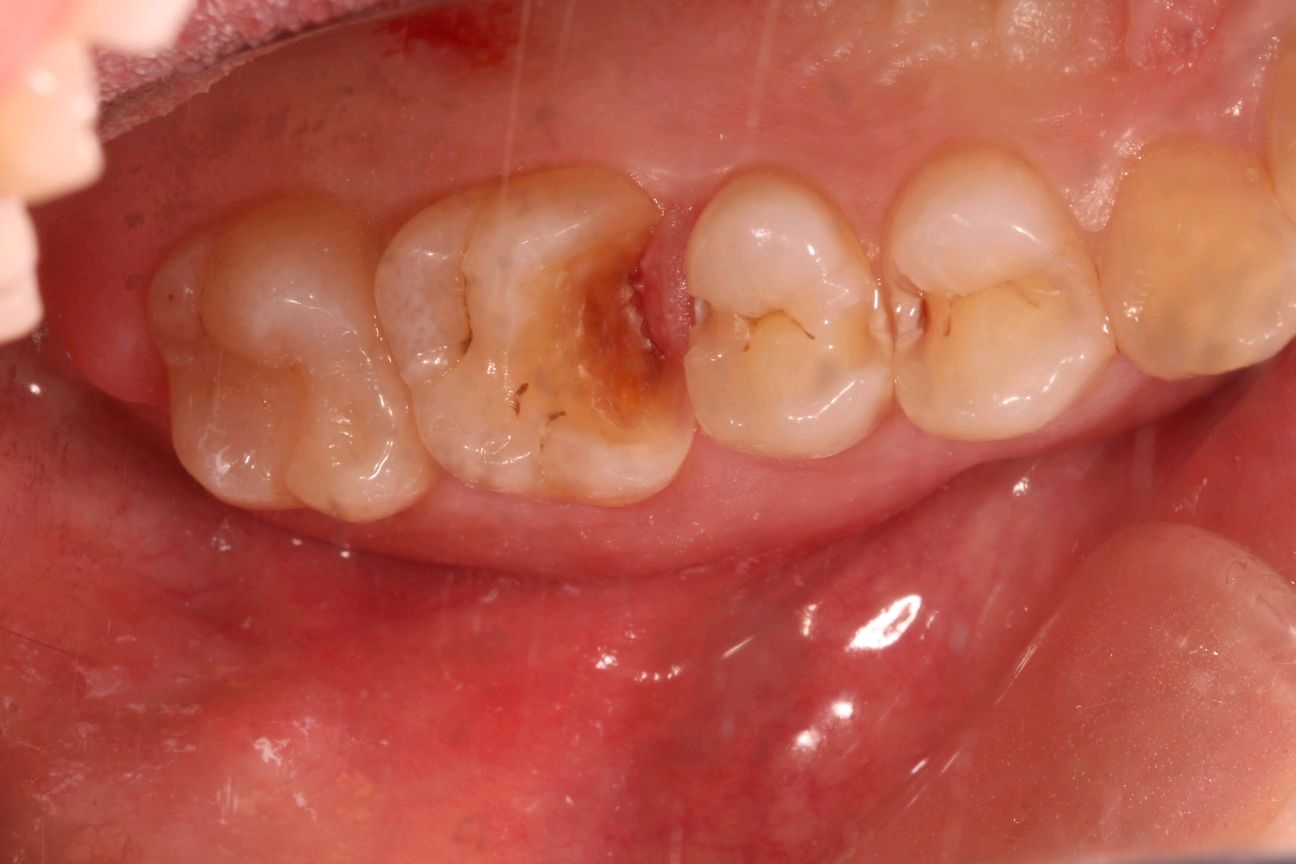

客户诉牙齿进食冷热酸痛敏感,检查发现各牙邻接面龋坏,告知患者各种备选修复材料的优缺点、相应修复费用和修复时间、可能的复诊次数和并发症,患者选择了嵌体修复。

0.1%的聚维酮碘溶液局部消毒,涂表麻膏,4%盐酸阿替卡因肾上腺素注射液0.8ml局部浸润麻醉,等待麻药生效后。去净腐质,基牙预备基牙预备,排龈,精修,CEREC扫描,比色,CEREC制作嵌体,试戴后边缘密合,符合各种对修复体的质量和设计要求,患者满意,同意粘固。消毒基牙和修复体,酸蚀冲洗,隔湿,吹干,粘接做永久固定,调合抛光,交代注意事项,常规医嘱,按时复诊,客户表示一次就诊方便快捷,很满意。